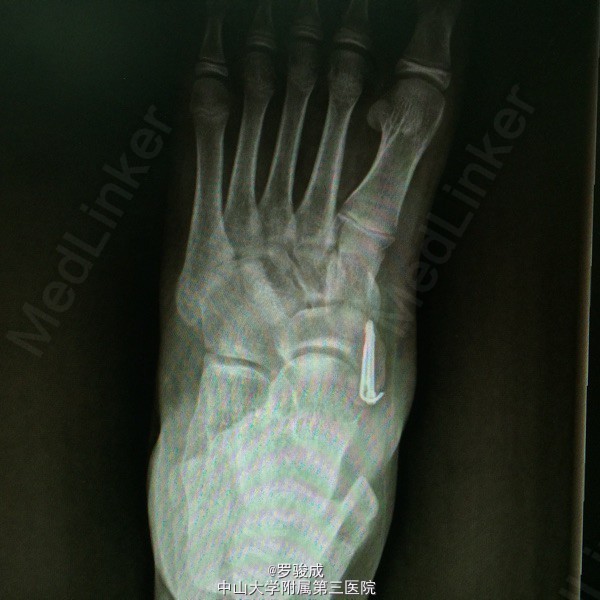

左足内侧疼痛2年余 两年余前运动后出现左足内侧疼痛,伴胀痛,无放射痛,无足部麻木。近来症状加重,遂前来我院就诊,X线提示左足副舟骨综合症。

左足内侧弓副舟骨表面硬性突起,无红肿,皮肤温度无升高,压痛明显。左足神经血运及感觉良好

诊断为左足副舟骨综合症。 行左足副舟骨清理融合术

足副舟骨综合症是一种先天性疾病,是舟骨结节部第二化骨中心的先天异常,在舟骨结节处形成一个独立的副骨。 足内侧隆起,久站或行走较长时, 感足底内侧疼痛。